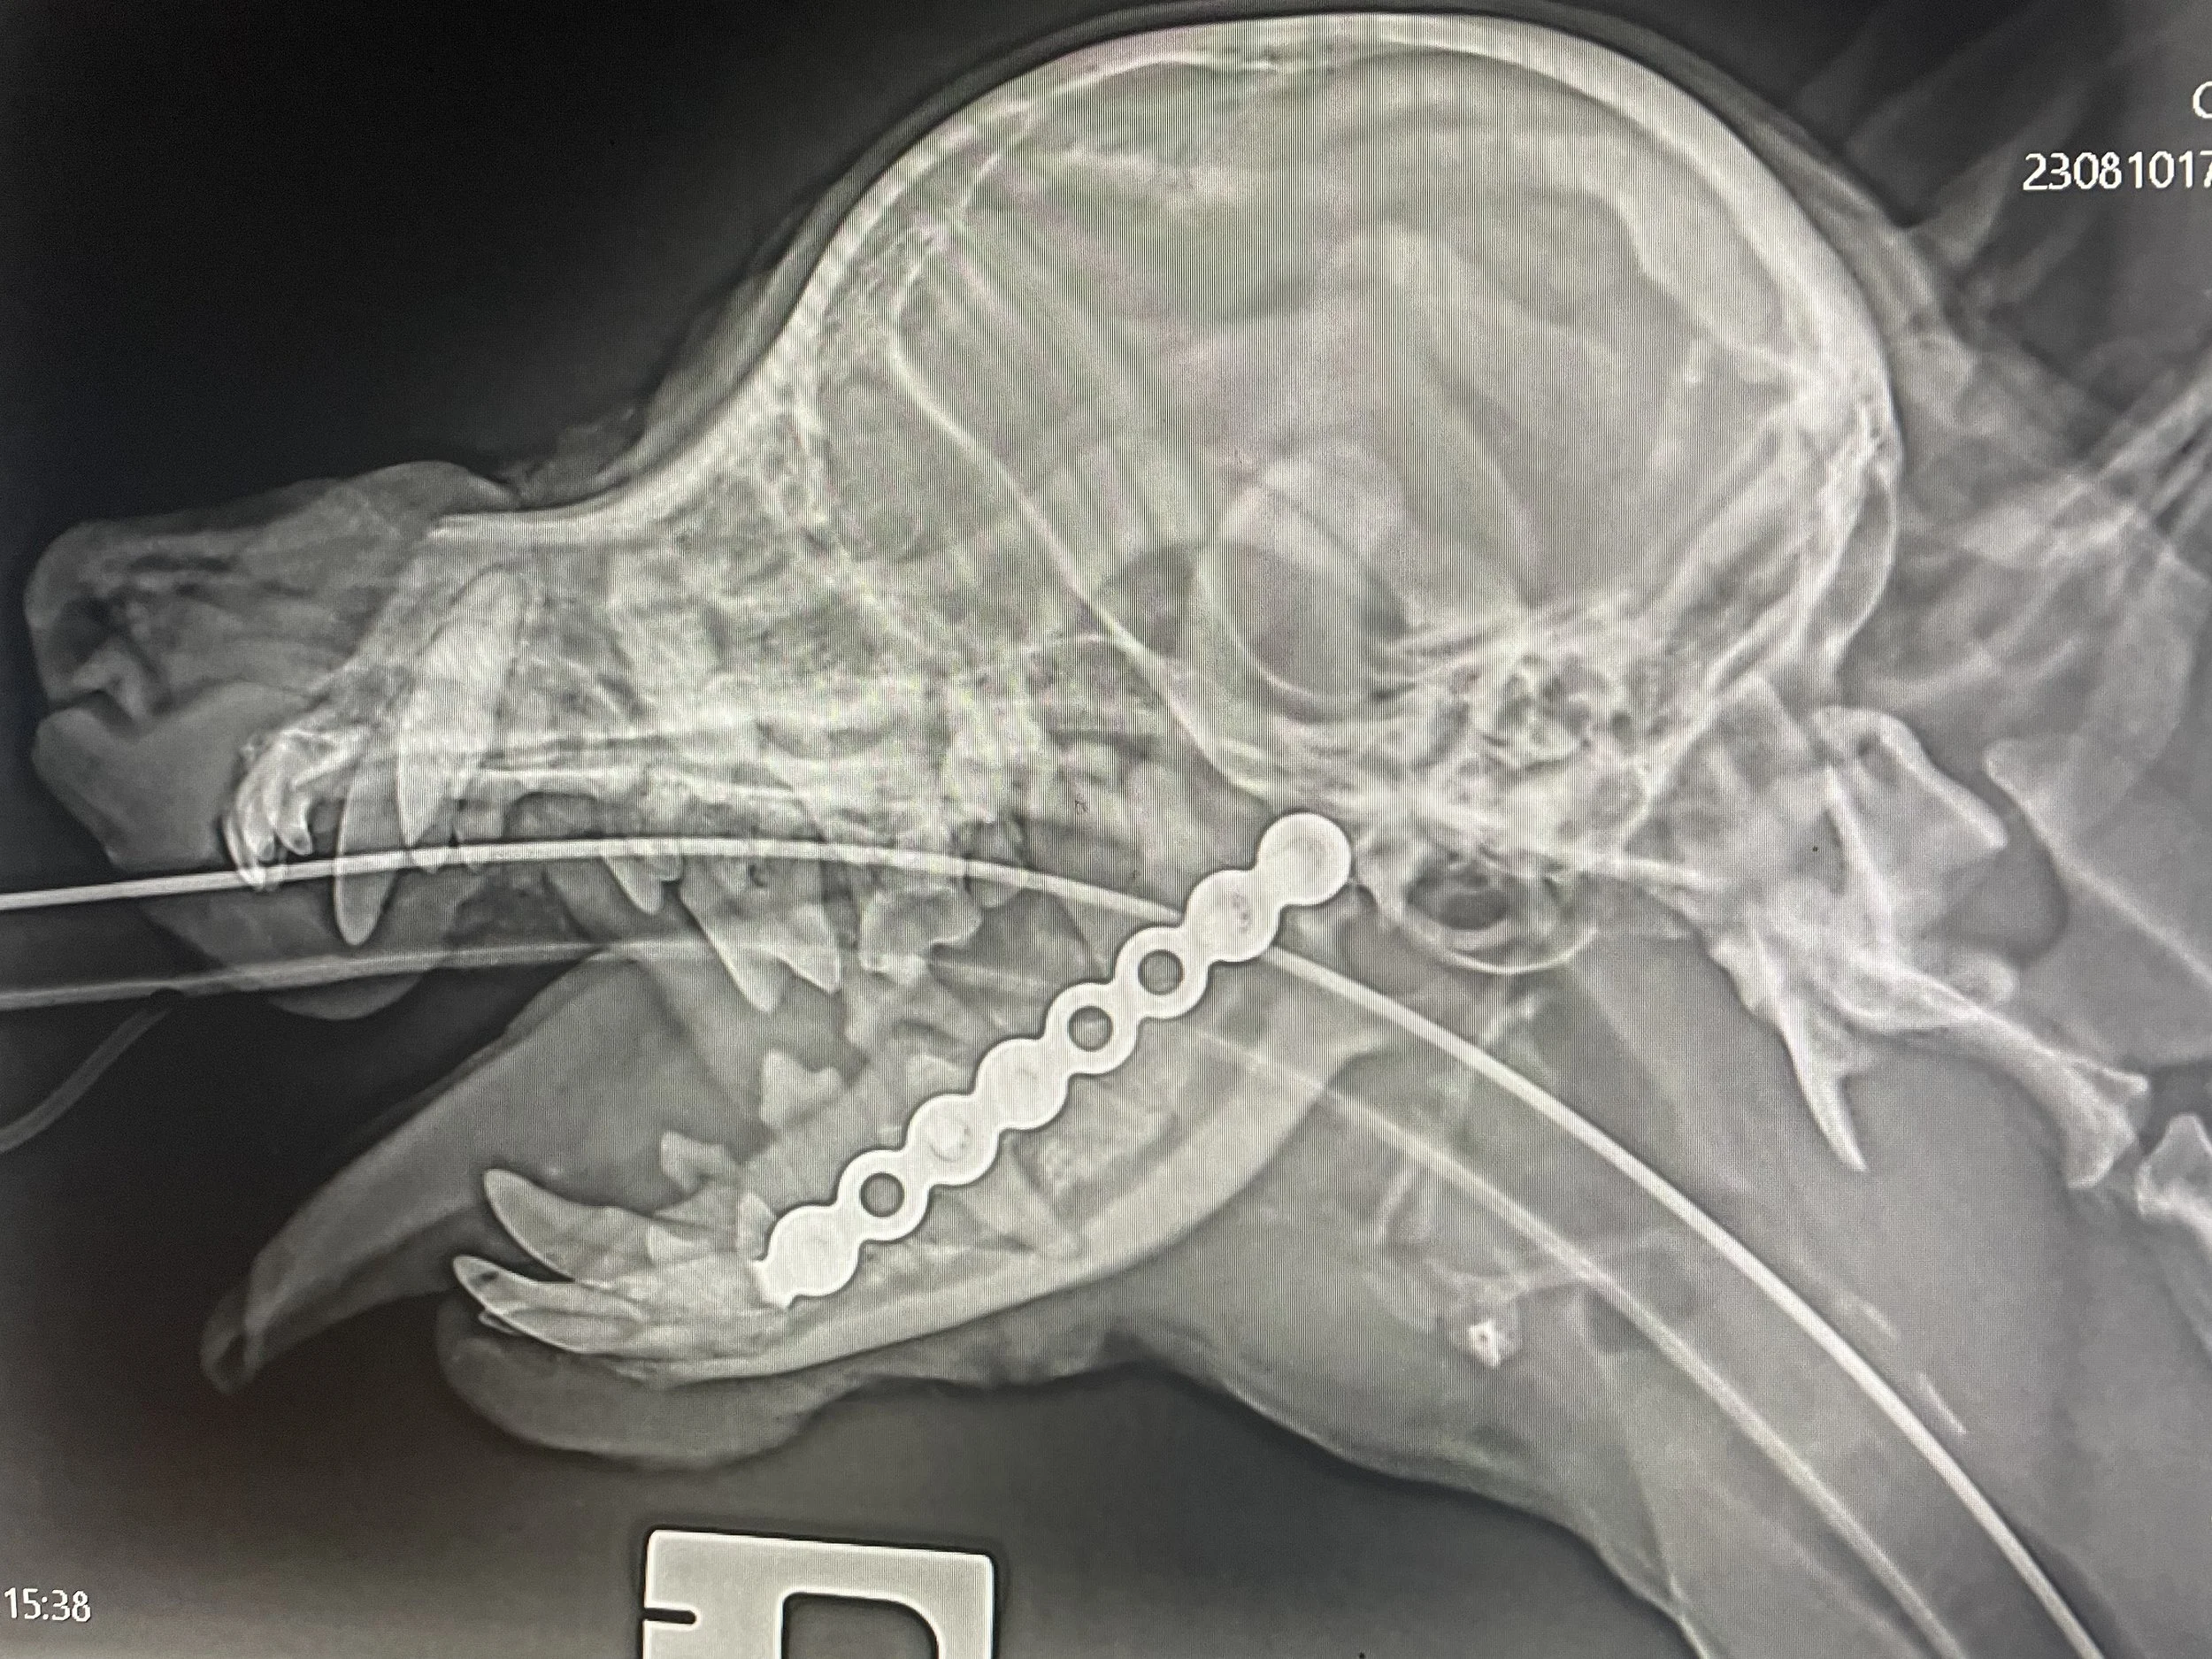

Fracture Repair

Dr Davids has a wide range of experience in fracture repair, and has attended numerous courses & workshops over the years. Please use the Contact Us page for further enquiries.